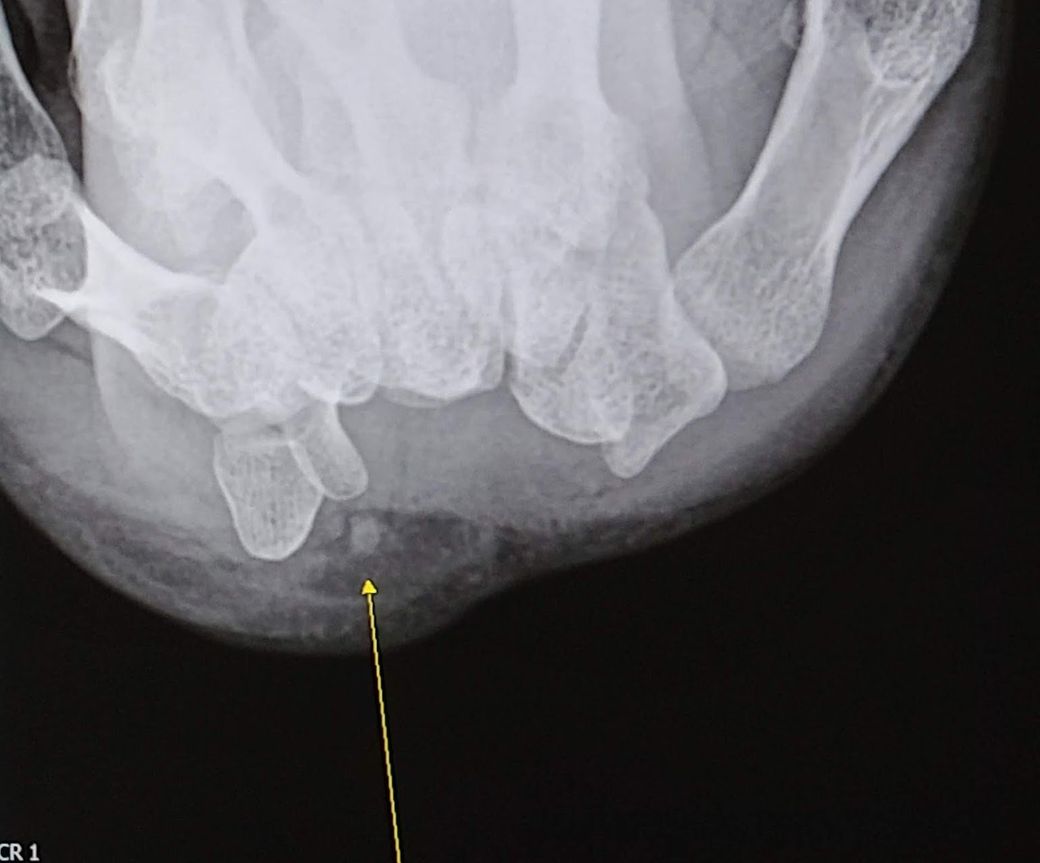

오른손목의 콩알뼈 부근에 일상생활을 영위하기 불편할 정도의 통증이 있습니다. 가만히 손목을 둘 때는 괜찮지만 물컵 이상의 무게 있는 물건을 들거나 팔을 사용해 짚게 되면 시큰한 통증이 콩알뼈를 쿡 쑤시듯 찾아옵니다. 컴퓨터 작업을 오래 하면 콩알뼈 부근이 점점 시려오구요. 덕분에 가급적 왼손으로 생활하고 있습니다.

직업상 키보드와 마우스를 많이 만져서 발병한 증상이라고 하며 처음 진단받은지 2년이 넘었습니다. 손목 콩알뼈 주변 힘줄에 염증이 생긴 거라고 들었고, 엑스레이 상으로 석회도 발견됩니다. 재활의학과와 정형외과를 다녔고 도수치료와 체외충격파 치료도 열번 가량 받아봤지만 차도가 없었습니다. 주사를 맞으면 조금 덜 아프다가도 몇 달이 지나면 다시 통증이 옵니다. 지금까지 주사를 팔꿈치에 두 번, 손목에 두 번 맞았습니다. 병원에서도 해줄 게 없다고 주사를 맞아도 그때뿐이며 점점 자주 맞아야 할 거라고 손목을 쉬거나 대학병원에 가보라고 합니다. 그래서 최근에는 휴직 후 1달 이상 쉬고 있는데도 통증은 이상하게 더해 가기만 합니다.

• 1번 째 사진